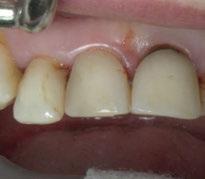

Figura 26. Entrega del provisional de carga inmediata a las 24 horas.

Figura 27. Ortopantomografía del provisional atornillado en boca para verificar ajuste.

ortopantomografía de verificación del ajuste pasivo de todos los implantes. Por último, tapamos las chimeneas con teflón y resina provisional y se chequeó nuevamente la oclusión, dando nuevamente las instrucciones de higiene y mantenimiento de la prótesis provisional (Figuras 24-27).